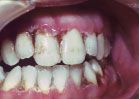

It is well known in the dental community that the emergence of the HIV infection in the early 1980s was accompanied by an explosion of some common and some rarer oral conditions including candida infections, Kaposi’s sarcoma, hairy leukoplakia, and a variety of other bacterial infections. In addition, HIV-associated infections associated with the periodontium included a linear gingival erythema (Fig. 3), necrotizing gingivitis (Fig. 4), human papilloma virus, and most seriously a necrotizing periodontitis with both soft- and hard-tissue necrosis that could extend beyond the periodontal tissues (Figs. 5-7).

While candida infections often were an early indicator of HIV infection and the beginning of the decline in immune status, necrotizing periodontitis in these patients was usually an indication of a severe decline in immune function and marked increase in the HIV viral load as the patient progressed to full-blown AIDS. However, with the advent in the early 1990s of a combination of antiretroviral drugs and new antiviral approaches known as HAART (Highly Active Antiretroviral Therapy), there was a marked decline (and in some cases a near complete disappearance) of some of these more serious oral/periodontal lesions, as viral levels remained suppressed and immune function was preserved.